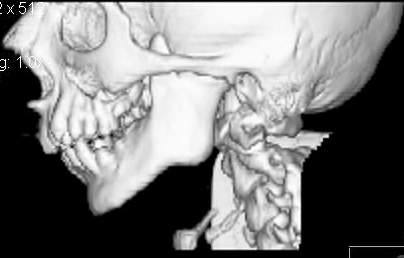

Пациент В., 13 лет. Диагноз: Костный анкилоз левого височно-нижнечелюстного сустава (ВНЧС), левосторонняя микрогения. Болеет с 2-х летнего возраста. Возможная причина развития анкилоза – воспалительный процесс (в первые 1,5 года жизни часто болел простудными заболеваниями, травму родители отрицают). В 3 и 5 лет проводилась редрессация – безуспешно. Прилагаются: ортопантомограмма, кадры СКТ с 3Д реконструкцией. Вопросы: определение тактики лечения – вид и сроки реконструктивно-пластической операции (этапов операции), а именно – неоартропластики и устранения микрогении, медикаментозная терапия в до- и послеоперационный период, ортодонтическое лечение.